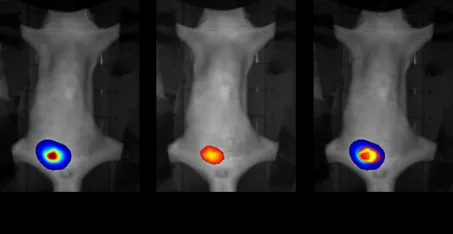

在肿瘤学研究中,设备的价值尤为凸显。科研人员可将荧光素酶基因稳定整合到肿瘤细胞中,构建荷瘤小鼠模型。通过活体成像,能够清晰观察肿瘤细胞在小鼠体内的定植、增殖过程,精准测量肿瘤体积的动态变化,甚至可以追踪肿瘤细胞的转移路径——从原发灶到淋巴结、肺、肝等远端器官的扩散过程被直观呈现,为解析肿瘤转移机制提供了直接的视觉证据。

在抗肿瘤药物研发中,该设备更是高效的“疗效评估工具”。在药物干预过程中,通过定期活体成像,可实时监测肿瘤区域的光学信号强度变化,快速判断药物对肿瘤生长的抑制效果,相比传统的肿瘤称重法,不仅缩短了实验周期,还能实现对同一动物的长期连续观测,减少了实验动物的使用量,同时提高了数据的可靠性。例如,在免疫检查点抑制剂的研究中,设备可清晰呈现免疫细胞浸润肿瘤组织的过程,为药物作用机制的解析提供了可视化依据。

原位前列腺肿瘤(荧光素酶进行生物发光标记)

三维成像,精准定量定位